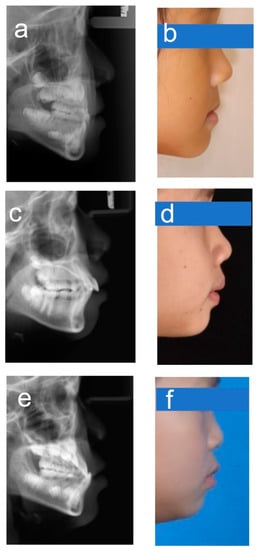

Figure 6. Example images for borderline cases. (a,b) Class I–III; (c,d) Class I–II; (e,f) Class III–I.

Automated diagnosis based on deep learning has gained widespread attention as a practical clinical aid for diagnosis of patients with many different diseases. Previous studies have not reported any automatic skeletal classifications for children whose facial morphology and trends differ significantly from adults. For the automatic categorization application of the sagittal skeletal relationships in children, we trained a representative CNN model, DenseNet-121, by using 1613 lateral cephalograms. Under the conditions used for transfer learning, it was found that this CNN model could be trained without difficulty in under 90 min. It was clear that this CNN model could accurately classify sagittal skeletons of children, with >90% accuracy and >0.96 AUC after the data were subjected to a 5-fold cross-validation test. The accuracy obtained was lower than that observed for adults [25,26], which may be because pediatric patients are likely to be undergoing rapid growth changes. In addition, the shape of the skeletons dramatically varies with age, which can further complicate the diagnosis of younger patients. For instance, individuals with anterior crossbites who are too young to be properly classified may not have visible skeletal deformities yet. Furthermore, despite careful annotation, there would still be many labeling ambiguities in the close proximity of the two classification boundaries, and this can compromise overall accuracy. According to our results, the majority of the misclassified instances were boundary cases that even well-experienced experts had trouble correctly classifying. These cases fell into one of two categories and were mainly found in patients with skeletal Classes II and III (Figure 6). Additionally, we produced a subset of data (AP-sub) that was free of borderline cases and found that the accuracy increased from 90.3 to 94.05%, thus providing additional evidence that the borderline cases affected the overall accuracy of our results.